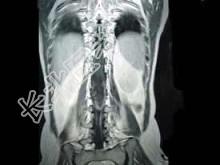

- 单项选择题男,43岁, 背部疼痛,双下肢瘫痪, 查体:下腹部以下深浅感觉障碍, 提睾反射消失,结合图像, 最可能的诊断是 ( )

A、星形细胞瘤

B、脑膜瘤

C、神经鞘膜瘤

D、神经纤维瘤

E、髓内室管膜瘤